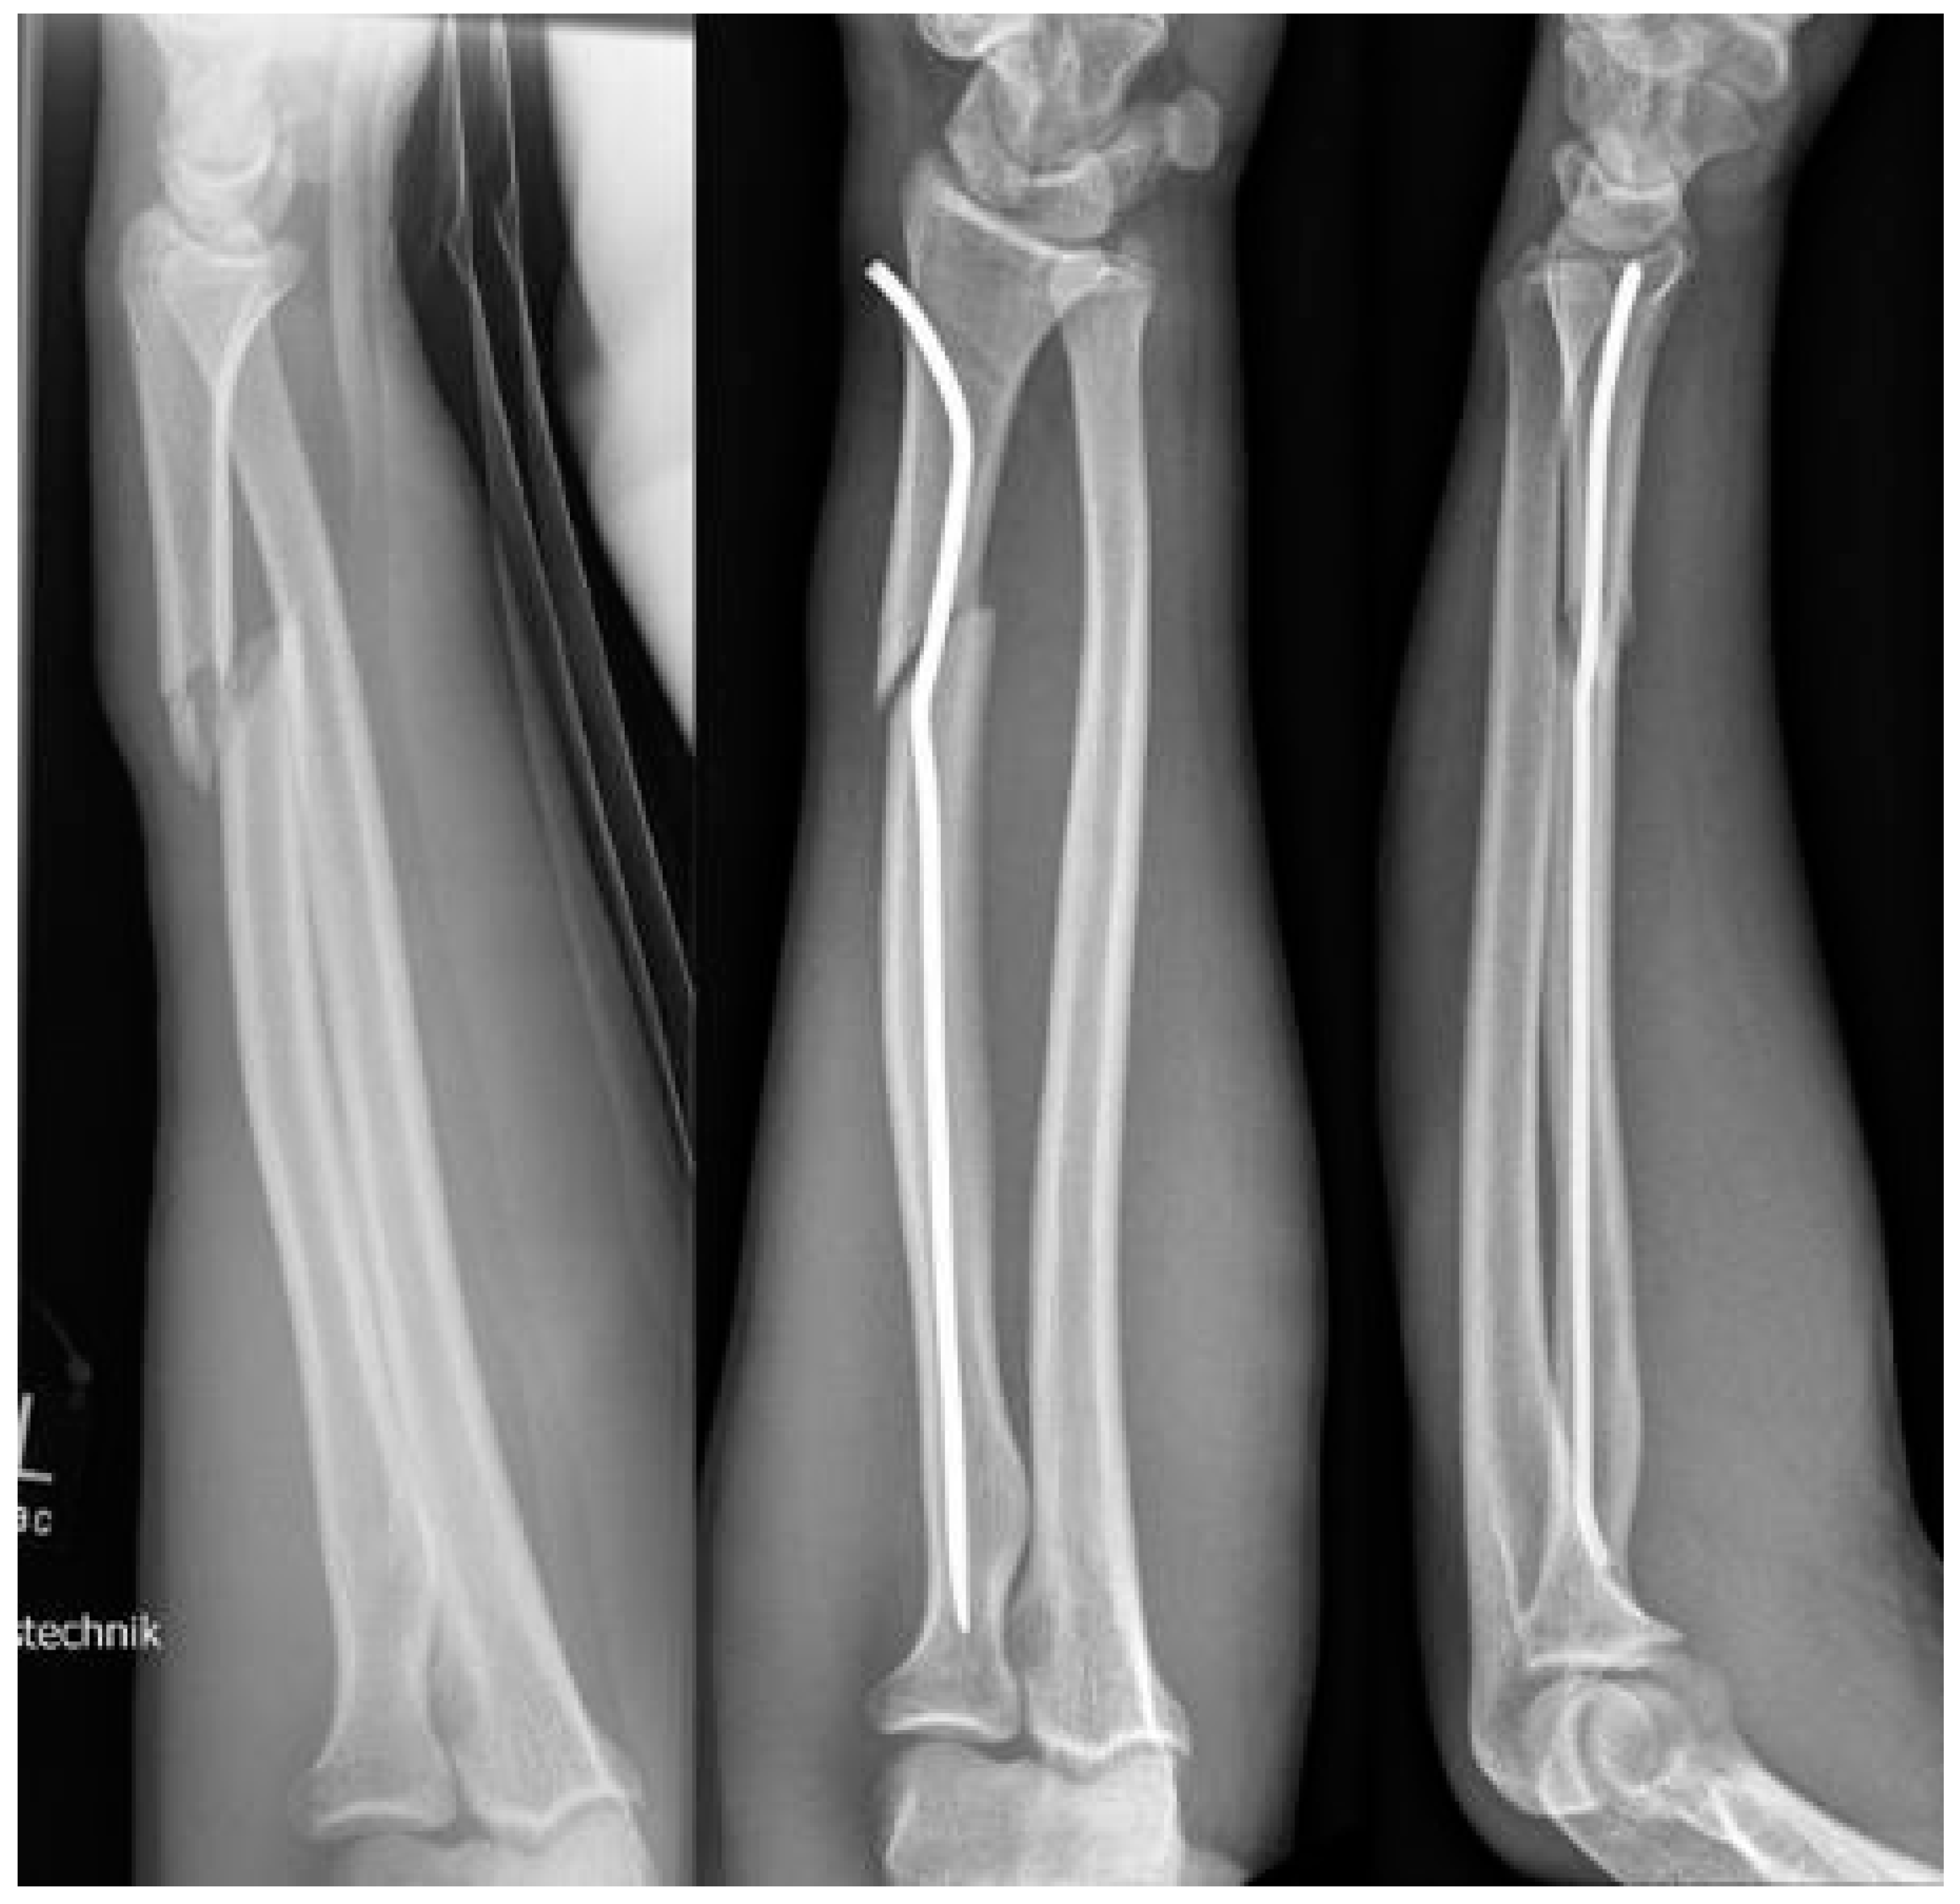

After choosing the right diameter (which should not be as big as possible: about half the diameter of the intra-cortical space is ideal), the distance between skid and the proximal kink must be established. To avoid x-ray exposure to the surgeon’s hand, the nail is grasped with forceps and is placed on the patient’s arm, skid facing upwards. Under fluoroscopy, the position of the first kink is determined about 1 cm proximal to the fracture (skid must be distal to the growth plate of the proximal radius) and is marked by bending the nail slightly (the final bend of about 45° should be performed later: if it is performed now, the nail will not fit into the handpiece, see Figure 2). Now, a skin incision is performed, lateral of the distal radial growth plate, and the radial metaphysis is perforated, just proximal to the growth plate, as in ‘normal’ intramedullary nailing. The nail is introduced into the bone until the kink appears between the bone and handpiece: now the kink is completed to at least 45°. This is the important moment; the second kink must be performed, about 2–3 cm distal to the first kink (the distance between the kinks equals about twice the diameter of the radius in the region of the fracture), in the opposite direction to the first kink, again at least 45° (Figure 2). The nail can be bent to modify the distal kink (Scheme 1); however, the aim is that this kink finally gets contact to the ulnar-sided cortical of the radius and leads to a tension-free curve to the area of insertion.

Figure 2. Determine diameter of nail and distance between skid and proximal kink (fluoroscopy). The skid should finally be placed in the radial neck, the first kink 1 cm proximal of the fracture. The second kink is performed before the first is pushed into the bone.